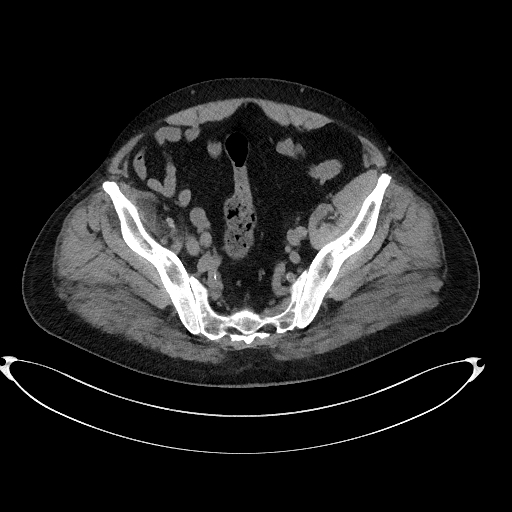

Figura 4: reconstrucție oblic axială din achiziție CT fără contrast control după 22 luni

Discuţie caz nr 134: Pe imaginile achiziționate fără substanță de contrast se remarcă creștere marcată de volum a muschiului ilio-psoas drept în două treimi distale cu evidențierea unei plaje întinse cu densități sangvine ce sugerează prezența unui hematom posttraumatic; nu se evidențiază traiecte de fractură. Achiziția de control după 22 de luni evidențiază reducerea grosimii corpului muscular ilio-psoas drept cu încărcare grăsoasă care, pe alocuri, afectează aproape complet corpul muscular.